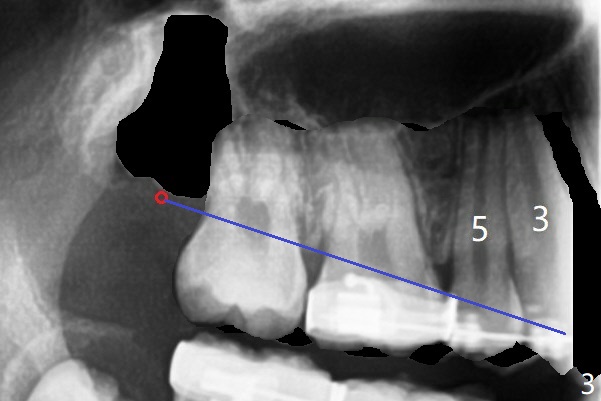

While the left posterior interdigitation is normal, the right is a half tooth off (Class II) 2.5 years post banding (16 years old, male, Fig.1). The upper midline remains left. The roots of the upper anterior teeth are within normal limit. UR8 will be extracted with bone graft (sticky bone; Fig.2). A 8 mm mini implant or a DIO 1-piece implant with ball abutment will be placed in the same appointment if possible (red circle). With a closed coil spring, UR3-7 or 1-7 will be distalized en bloc (Fig.3). Take photos for the occlusion: right, middle and left.